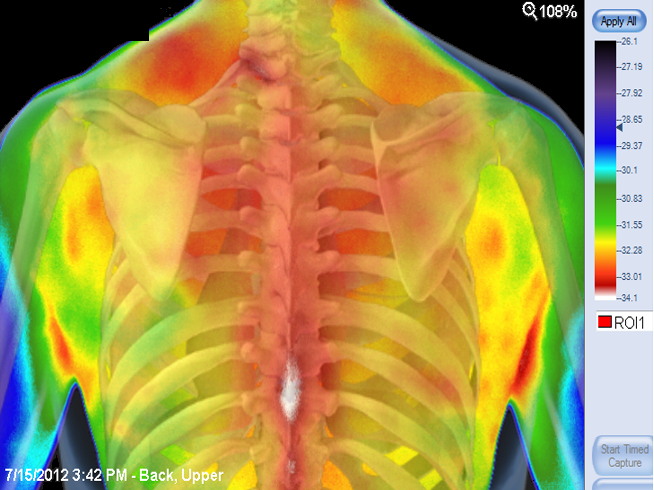

- Rapportage mogelijk over alle lichaamsdelen.

- Temperatuurvergelijkingen vanuit diverse posities/beelden bekeken.

- Herkenning van verdachte lichamelijke veranderingen in het patroon.

- Aandacht voor verdachte patronen in de verandering van temperatuur wanneer deze betrekking hebben op: